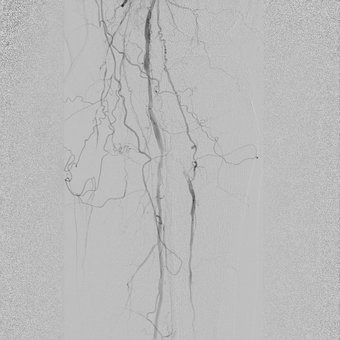

— У пациентов с синдромом диабетической стопы, к сожалению, чаще выполняется ампутация конечности, чем попытка восстановления кровотока в пораженной конечности. Хотя на сегодняшний день возможности сосудистой и эндоваскулярной хирургии позволяют если не сохранить конечность целиком, то хотя бы сберечь ее опорную функцию, тем самым сохранив пациенту мобильность, а значит и высокое качество жизни. Эта пациентка поступила к нам с сухой гангреной без инфицирования 1, 2, 3 пальцев правой стопы 2А степени по классификаци Техасского университета. Была предпринята попытка эндоваскулярной реконструкции пораженных артерий бедра и голени, критическое сужение или окклюзия которых и приводит к синдрому диабетической стопы и необходимости ампутации. Нами была выполнена реканализация подколенной, передней большеберцовой артерии и малоберцовой артерии правой ноги. Полностью пройти подошвенную дугу и заднюю большеберцовую артерию не удалось, но, несмотря на это, полностью был восстановлен кровоток в стопе и пальцах.

![]() Окклюзия подколенной артерии |